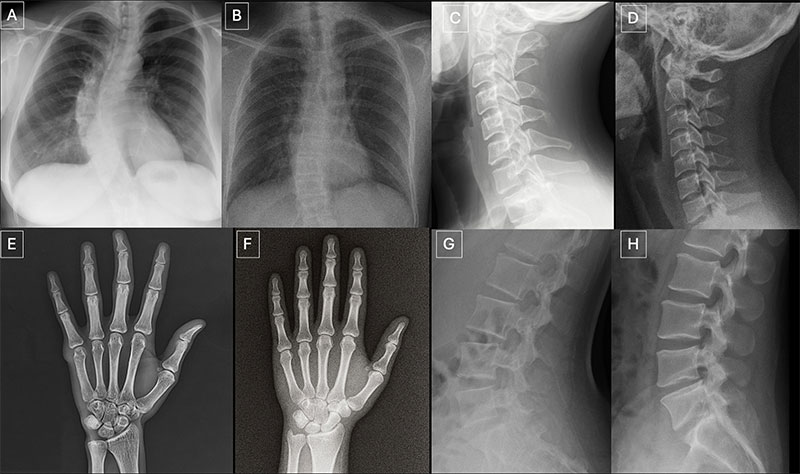

Anatomy-matched real and GPT-4o-generated radiographs: (A) real and (B) GPT-4o-generated posteroanterior chest radiographs, (C) real and (D) GPT-4ogenerated lateral cervical spine radiographs, (E) real and (F) GPT-4o-generated posteroanterior hand radiographs, and (G) real and (H) GPT-4o-generated lateral lumbar spine radiographs. The pairs demonstrate that GPT-4o can produce radiographically plausible images across different anatomic regions.

"Deepfake medical images often look too perfect,” Dr. Tordjman said. “Bones are overly smooth, spines unnaturally straight, lungs overly symmetrical, blood vessel patterns excessively uniform, and fractures appear unusually clean and consistent, often limited to one side of the bone."